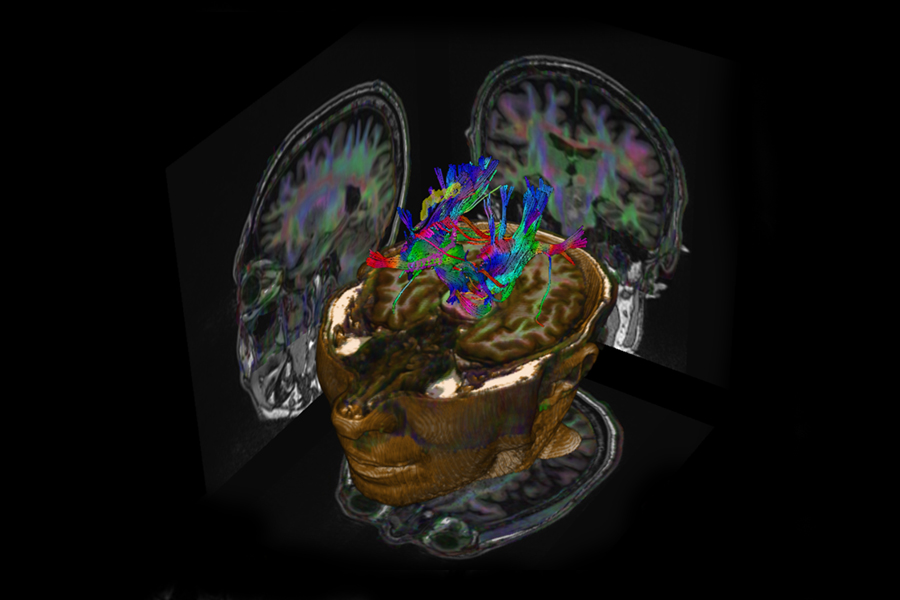

Die Magnetresonanztomographie (MRT) ist ein bildgebendes Verfahren, das mittels starker Magnetfelder und Radiowellen detaillierte Schnittbilder des Körpers erzeugt. Die Methode eignet sich besonders gut für die Untersuchung von Gehirn, Rückenmark und Wirbelsäule, inneren Bauch- und Beckenorganen, sowie von Muskeln und Gelenken. Abgesehen von der Darstellung der Anatomie lassen sich mithilfe der MRT auch funktionelle und dynamische Prozesse, wie etwa Stoffwechselvorgänge im Gehirn abbilden.

- Kopf und Gehirn

Am Zentrum für Radiologie und Neuroradiologie stehen uns Kernspintomographen der neuesten Generation mit 3 Tesla und 1,5 Tesla Feldstärke zur Verfügung. Die Geräte ermöglichen hochauflösende MRT-Untersuchungen aller Körperregionen. Die detaillierten Bilder erlauben es uns, erkrankte Organe erkennen und beurteilen zu können. Gemeinsam mit den Fachabteilungen des Klinikums und den niedergelassenen Spezialisten entwickeln wir dann eine individuelle Therapie für unsere Patientinnen und Patienten.